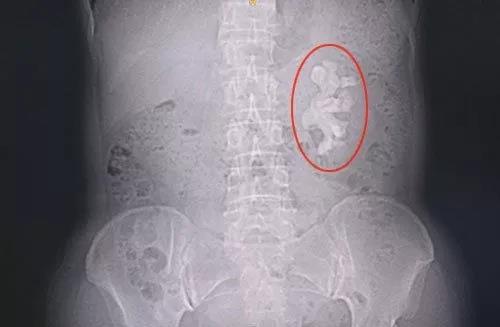

诊断报告显示:右肾见高密度致密影,右肾盂、肾盏被其填充,左肾下肾盏内见径线约4.5cm高密度影。双侧肾盂、肾盏未见明显扩张、积水。相当于双侧输尿管行径区未见明显异常高密度影。膀胱密度均匀,壁光滑。腹腔及腹膜未见肿大淋巴结,腹膜腔未见积液。

影像诊断结果为右肾铸型结石,左肾结石。影像诊断结果与马医生诊断结果不谋而合。

右肾铸型结石,手术难度较大。